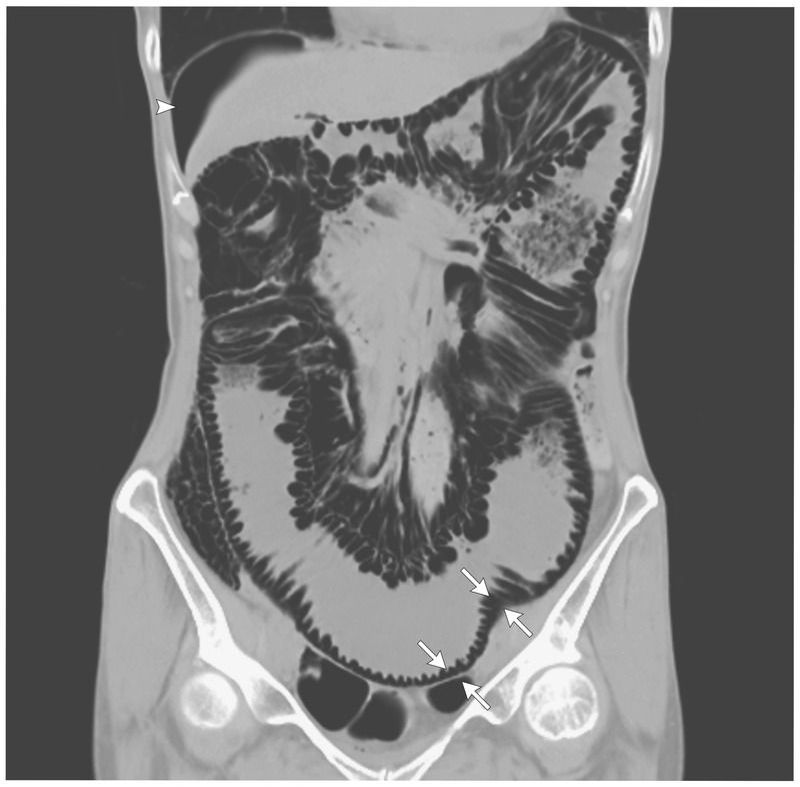

A 48-year-old woman presented to an outpatient clinic with a several-month history of abdominal fullness. She also had a history of eosinophilic pneumonia, which had been treated continuously with glucocorticoids for 7 years. On examination, her abdomen was distended but soft, with normal bowel sounds. Computed tomography (CT) of the abdomen showed air in multiple small cysts within the wall of the colon (arrows) and free air under the right hemidiaphragm (arrowhead), findings consistent with a diagnosis of pneumatosis cystoides intestinalis. This condition is characterized by the presence of numerous gas-containing cysts within the submucosal or subserosal layer of the intestinal wall. The pathophysiology is incompletely understood. Pneumatosis cystoides intestinalis may be associated with a range of gastrointestinal conditions, from intestinal ischemia to inflammatory bowel disease, as well as with endoscopic procedures, mechanical ventilation, and pulmonary diseases. Management of the condition is guided by the severity of the clinical presentation, which can vary on the basis of the underlying cause. The patient was admitted to the hospital, where she received supportive care, including oxygen administered through a face mask. Over the next 3 days, her abdominal symptoms decreased, and a repeat CT showed resolution of both the free air and the air in the intestinal wall.